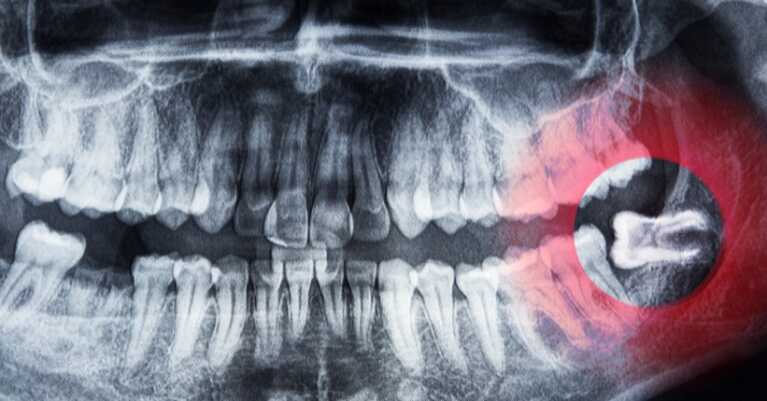

Hogyan diagnosztizáljuk az impaktált fogat?

Az impaktált fog diagnosztizálásához minden esetben szükség van képalkotó vizsgálatra, mivel a fog félig vagy teljesen az íny vagy a csont alatt rejtve helyezkedik el, és szabad szemmel nem látható pontosan. A Najudentben ehhez helyben biztosítunk korszerű panorámaröntgent és 3D CBCT-t, amelyek segítségével pontosan meg tudjuk határozni a fog helyzetét, dőlését, valamint azt is, mennyire van közel a szomszédos fogakhoz vagy az idegekhez.

Mivel minden szükséges vizsgálat rendelőn belül, kényelmesen elérhető, a páciensnek nem kell másik intézményt felkeresnie. A korai felismerés kiemelten fontos, mert minél előbb azonosítjuk a problémát, annál egyszerűbben kezelhető és elkerülhetők a későbbi szövődmények.